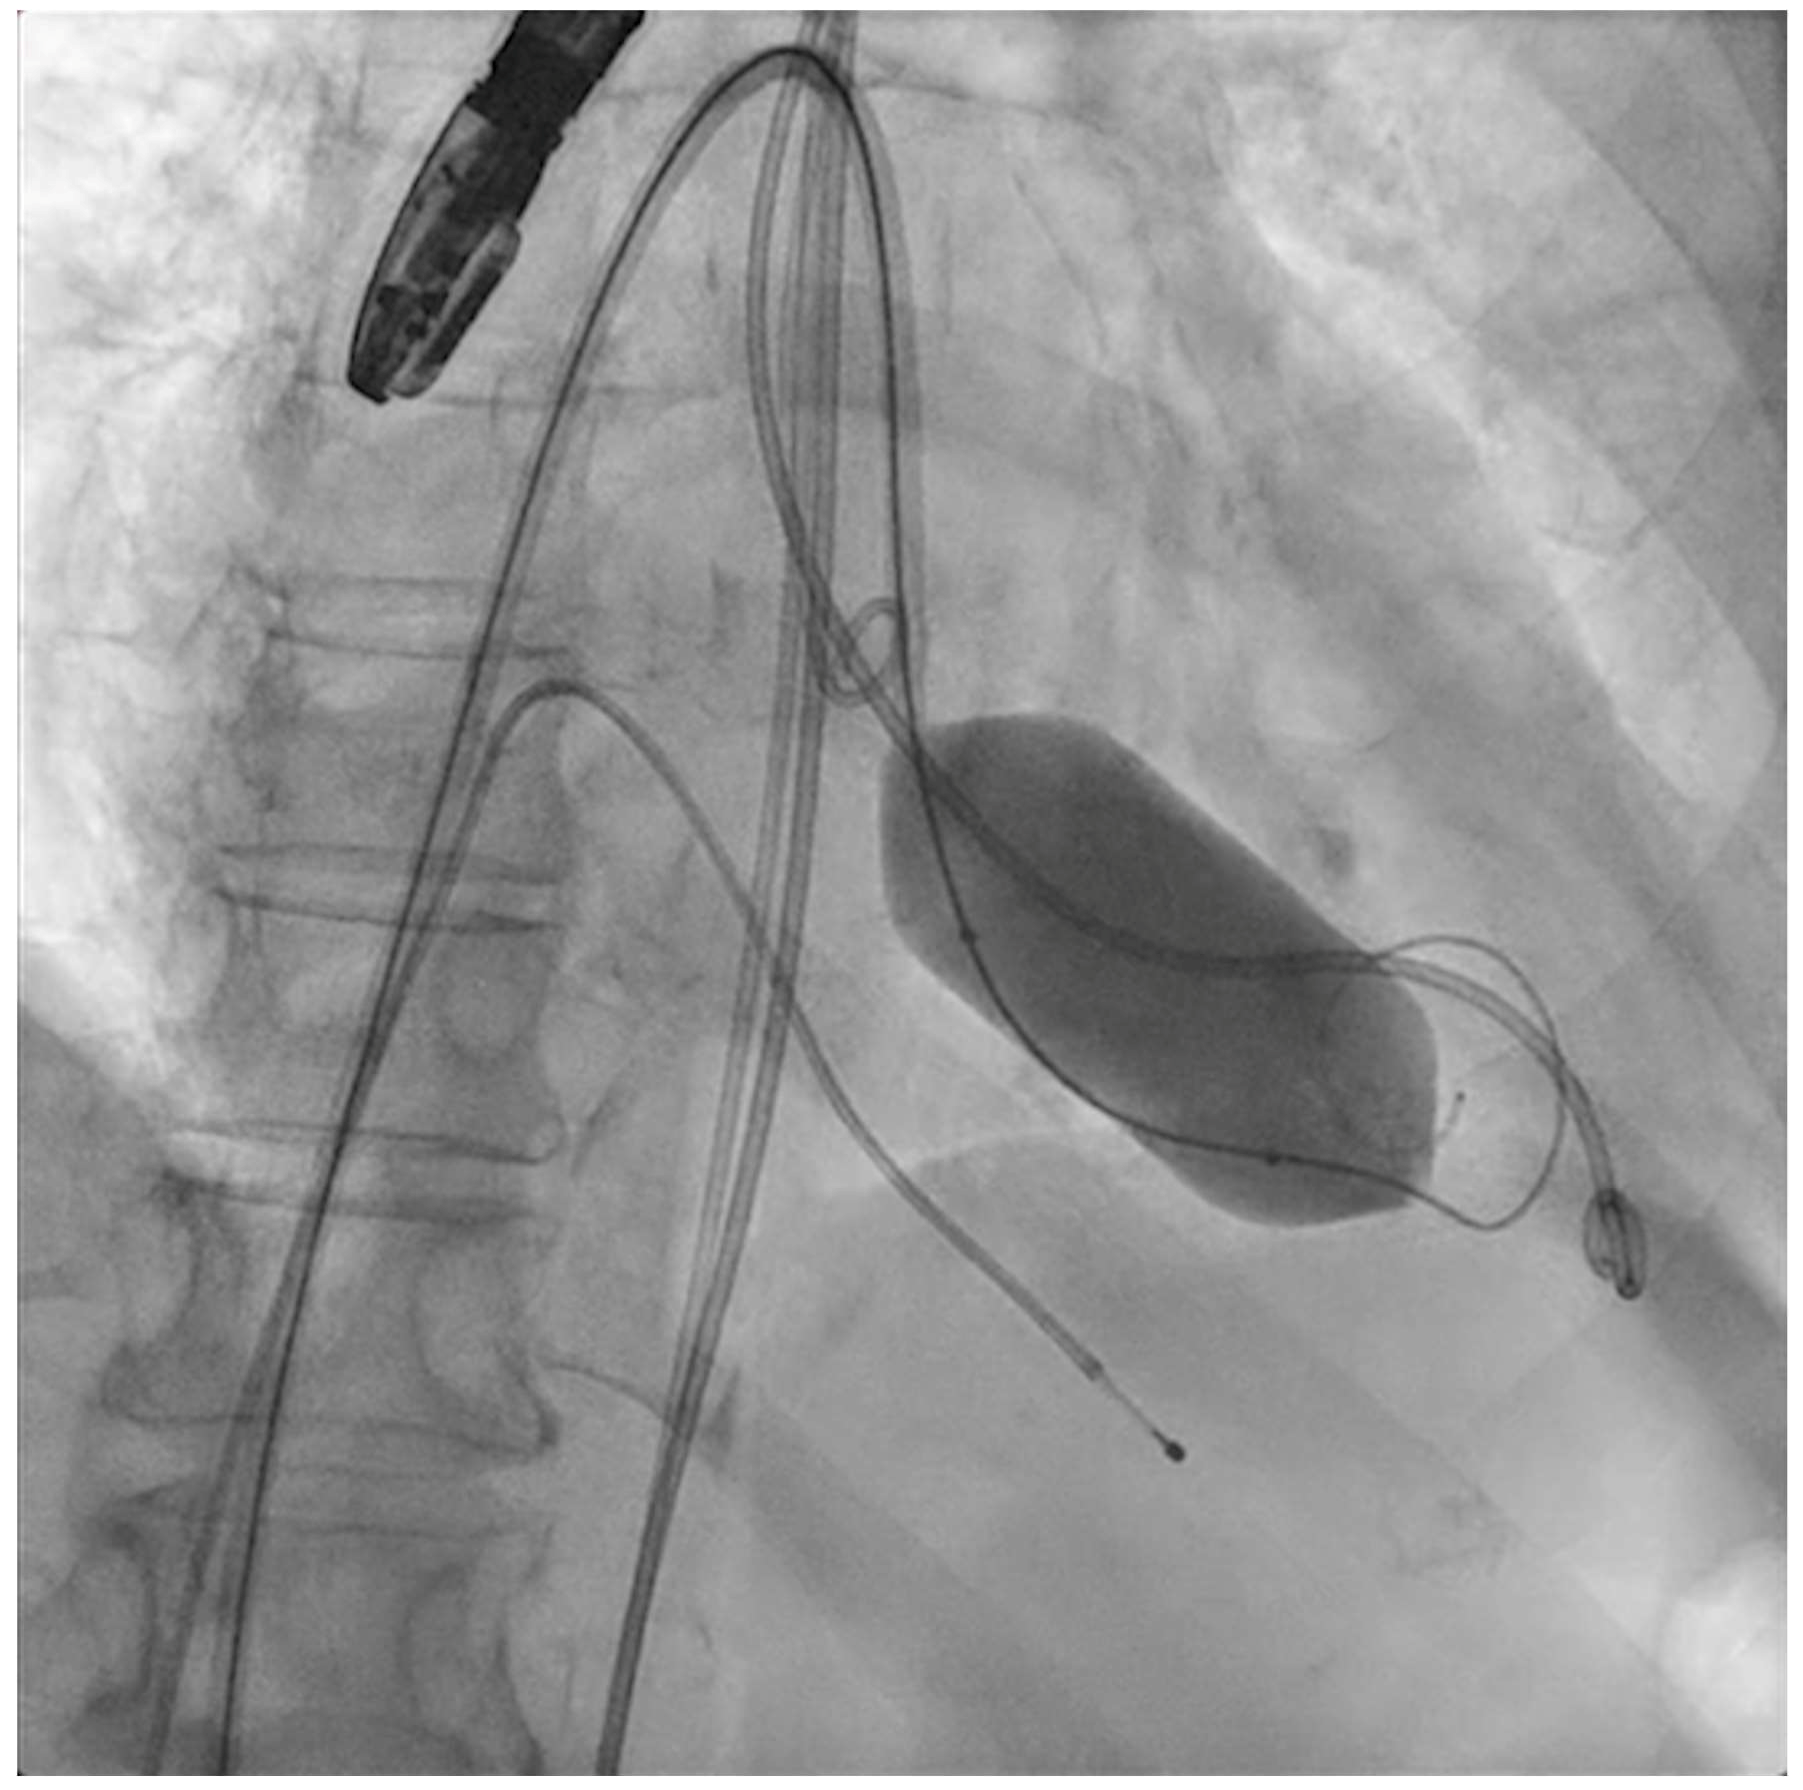

The next steps consist of crossing the mitral valve with three long high-support 0.014´´ wires downstream into the left ventricle (LV) (Figure 2) and then advancing three lithotripsy balloons (Shockwave Medical) across the mitral valve; with rapid pacing (120 beats/min), simultaneous inflations of all balloons will deliver a total of 90 pulses from each balloon (Figure 3). Finally, access to the LV has to be attained again with the Safari wire to complete PMC with large balloons appropriately sized to the mitral valve area and diameters (Figure 4). Embolic protection devices are encouraged to avoid neurological or systemic ischemic events due to calcific debris.

Figure 4.

Percutaneous mitral commissurotomy (non-compliant 26 mm balloon).